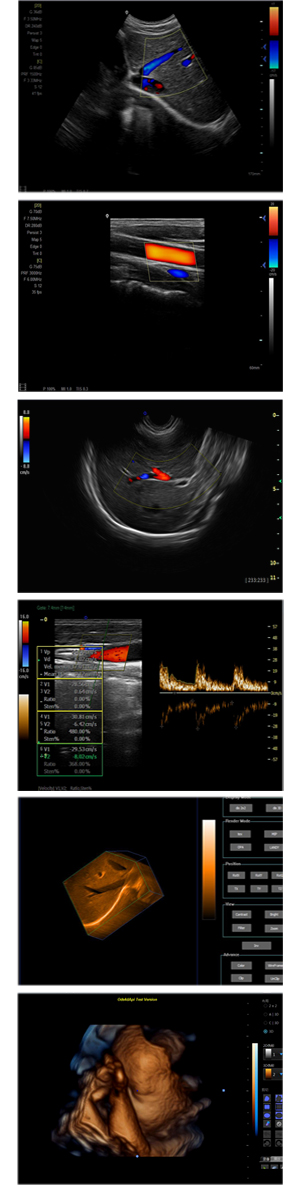

XF-7800型,秉承先鋒彩超技術之精華,擁有高雅大氣的獨特外型,為最新一代應用型數(shù)字彩色多普勒診斷系統(tǒng),魅力與實力相融合??蓮V泛適用于腹部、婦產(chǎn)科、心臟、小器官、乳腺、肌骨及外周血管等諸多方面的診查,讓您在臨床超聲診斷應用領域得心應手,綻放異彩!

● 3D/ 4D成像技術/限7800選配

● 應用于腹部、腎臟、泌尿系統(tǒng)、產(chǎn)科、婦科、盆腔、大動脈、肌肉組織、小器官、乳腺、心臟等

● 能量多普勒成像(PDI)

● 彩色血流量圖(CDE)

● 脈沖頻譜多普勒成像(PW)